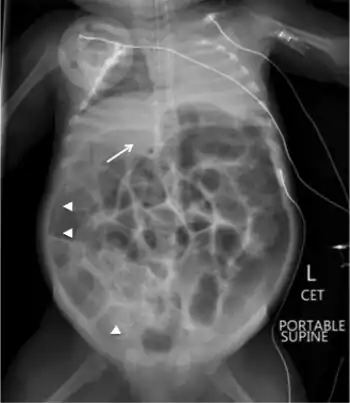

| (Fatal) Clostridial necrotizing enterocolitis in infant | |

An abdominal x-ray shows multiple dilated loops of small bowel and gas. The abdomen can be tender, distended, and soft. A differential diagnosis can be an intussusception.